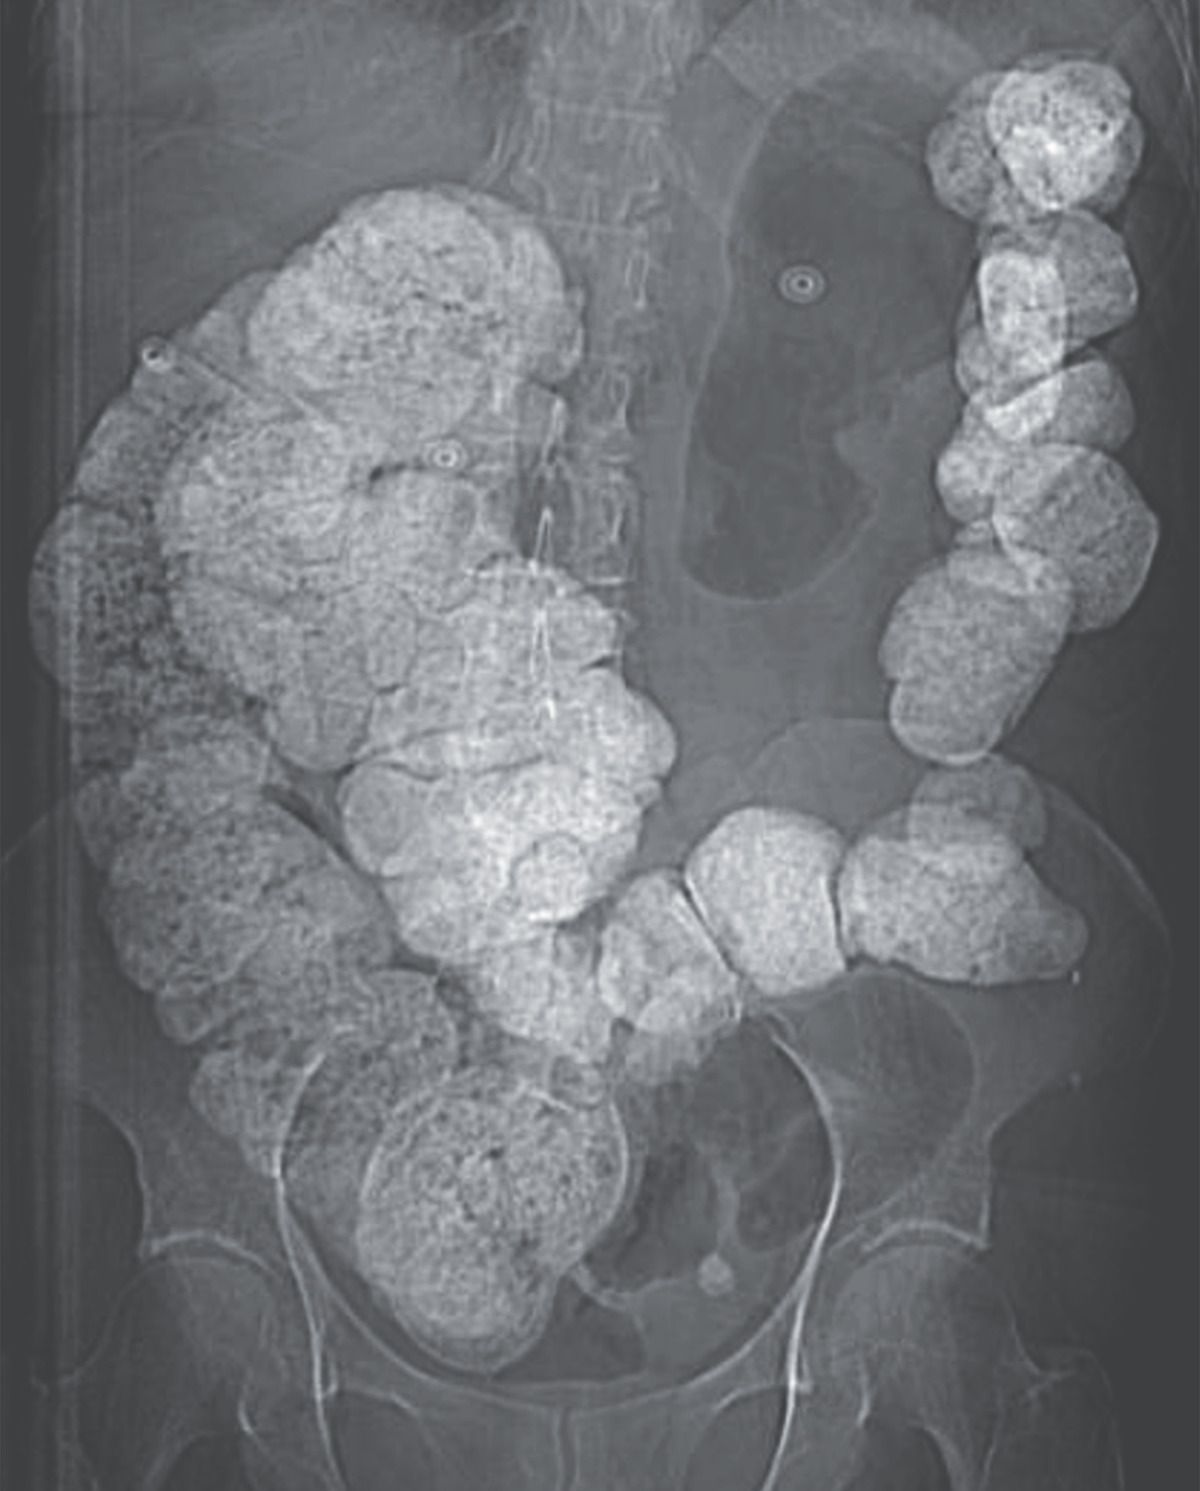

A 70-year-old woman with depression and irritable bowel syndrome presented to the emergency department with a 3-day history of altered mental status, shortness of breath, nausea, and vomiting. She had recently increased her daily intake of liquid bismuth subsalicylate, which she had been using for irritable bowel symptoms, to treat worsening diarrhea and abdominal pain. Physical examination was notable for a respiratory rate of 22 breaths per minute, confusion, and mild, diffuse abdominal pain. Laboratory testing showed primary anion-gap metabolic acidosis, primary respiratory alkalosis, and a salicylate level of 76 mg per deciliter (5.50 mmol per liter; normal value, <5 mg per deciliter [0.35 mmol per liter]). An abdominal radiograph, for which no oral contrast material had been administered, showed intraluminal radiopaque material throughout the bowel. A diagnosis of bismuth subsalicylate poisoning was made. Bismuth subsalicylate is metabolized to bismuth and salicylic acid in the gastrointestinal tract. Large quantities of bismuth appear radiopaque owing to the high density of the substance, which approaches that of lead. After treatment with sodium bicarbonate infusion and hemodialysis for salicylate poisoning, the patient’s symptoms abated; a repeat salicylate level was 0.